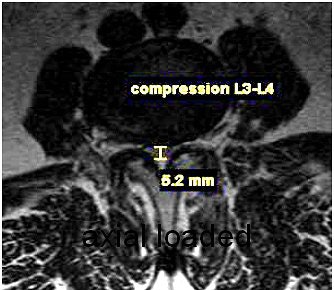

| Increased conspicuity of L4-L5 disk bulge and 2.0 mm increase in stenosis at the L4-L5 level with axial loading. |

A survey of patients from a private practice setting who underwent axial-loaded imaging demonstrated an increase in the conspicuity of focal disk bulging and herniation, as well as an increase an anterolisthesis or retrolisthesis ("Axial loaded magnetic resonance imaging of the lumbar spine in a chiropractic patient population," Proceedings of the 2006 Conference on Chiropractic Research, Chicago).

Dr. Akio Hiwatashi's group found that axial loading during MR imaging of the lumbar spine can influence treatment decisions for symptomatic spinal stenosis from conservative management to decompressive surgery based on the findings obtained from axial-loaded MR images (American Journal of Neuroradiology, February 2004, Vol. 25:2, pp. 170-174).